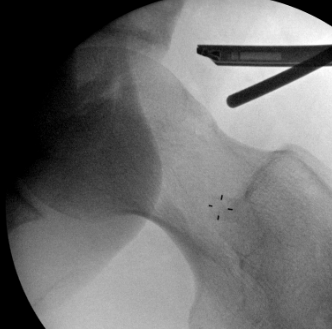

Portals

PALA - Proximal anterolateral viewing portal

- entry point anterolateral aspect greater trochanter

- image intensifer

- insert just above head to avoid translabral penetration (between acetabulum and labrum)

- typically 20 degrees posterior depending on patient size

- guide wire / dilators / cannula

PALA

Insertion of PALA under image intensifier